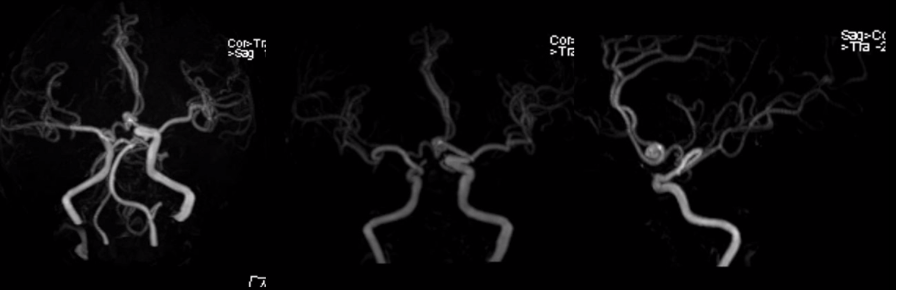

3.特殊类型的脑出血

(1)蛛网膜下腔出血

颅内血管破裂,血液进入蛛网膜下腔。

病因:动脉瘤破裂(最常见)、高血压、血管畸形、外伤。

(上下滑动查看全部图片)

(2)前交通动脉瘤破裂出血